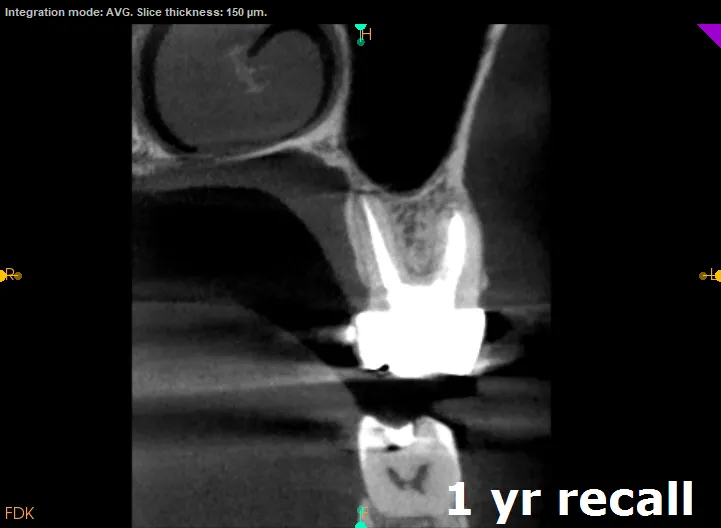

MB2 canal successfully negotiated, cleaned, and obturated. Patient asymptomatic at 2-year follow-up

The entire procedure took approximately 2 hours. The canal was successfully negotiated to full working length, cleaned with GentleWave technology, and obturated along with the other three canals.

At 2-year follow-up, the patient remains completely asymptomatic with radiographic evidence of periapical healing. The tooth is functional and the patient reports no sensitivity.